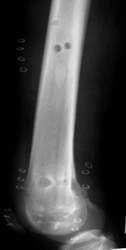

Oberschenkelfraktur bei einem 17-jährigen

postoperativer Befund |

belastbar nach 8 Tagen

Acht Monate nach der Operation wurde das Metall entfernt.

Die Entfernung durch das Knie hindurch machte keine Probleme. Der

Patient konnte nach 8 Tagen das Knie wieder frei bewegen. Da das Wachstum

weitgehend abgeschlossen war, gab es keine Beinlängendifferenz.